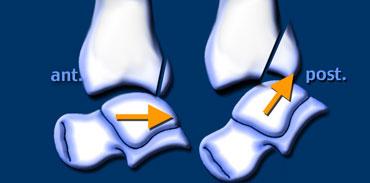

Loại gãy xương này được gọi là triplane (ba mặt phẳng) vì tổn thương xảy ra đồng thời trên mặt phẳng trán, mặt phẳng đứng dọc và mặt phẳng ngang.

Thực chất đây là gãy xương loại Salter-Harris type IV.

Loại gãy này gặp đặc trưng ở trẻ vị thành niên trong giai đoạn sụn tiếp hợp phía trong của đầu xương chày đã đóng, trong khi phần ngoài vẫn còn mở, khiến vùng này dễ bị tổn thương.

Do lực tác động không thể lan sang phần trong của sụn tiếp hợp vì vùng này đã đóng, đầu xương sẽ bị gãy.

Tương tự như hầu hết các gãy xương cổ chân, cơ chế chấn thương là xoay ngoài.

Tổn thương bao gồm:

- Gãy đầu xương trên mặt phẳng đứng dọc

- Tổn thương sụn tiếp hợp trên mặt phẳng ngang

- Gãy hành xương trên mặt phẳng trán